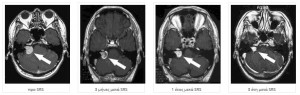

Ακουστικά Νευρινώματα

Τι είναι τα Ακουστικά Νευρινώματα.

To ακουστικό νευρίνωμα αποτελεί καλοήθη όγκο που προέρχεται από νευρικά κύτταρα της όγδοης κρανιακής συζυγίας που σχετίζεται με την ακοή και τη διατήρηση της ισορροπίας.

Αποτελεί όγκο που εξελίσσεται βραδέως προκαλώντας συμπτώματα όταν αυξηθεί αρκετά σε μέγεθος όπως οι εμβοές, η απώλεια ακοής, και οι διαταραχές στην ισορροπία.

Τα ακουστικά νευρινωματα, αν και καλοήθεις και βραδέως αναπτυσσόμενοι όγκοι λόγω της δύσκολης χειρουργικής προσπέλασης τους εξαιτίας της περιοχής που βρίσκονται- αλλά και την άμεση σχέση τους με το προσωπικό νεύρο, το ακουστικό νεύρο και το εγκεφαλικό στέλεχος αποτελούν μία από τις δυσκολότερες νευροχειρουργικές επεμβάσεις.